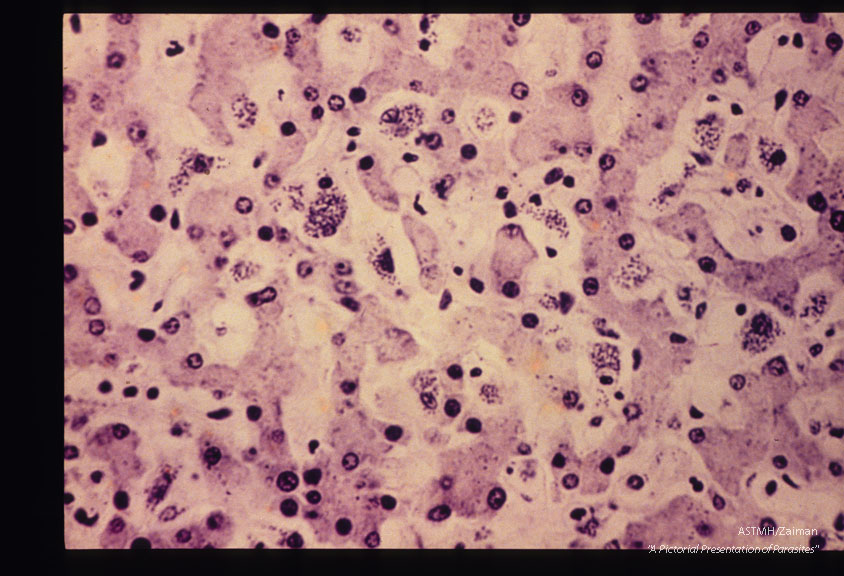

Leishmania donovani

Description: Liver